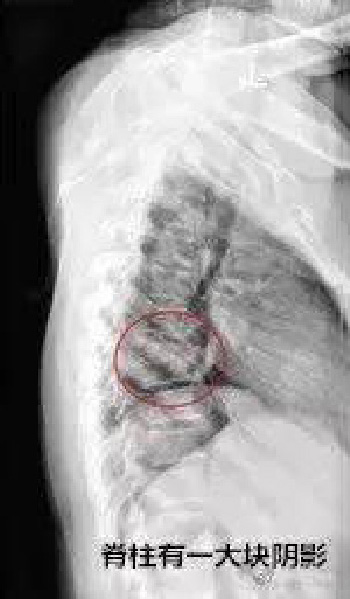

接诊后,医生给陈女士做了胸片检查,检查发现陈女士脊柱有一大块阴影,有可能是骨结核。通过 CT 检查发现,陈女士的胸 7、胸 8 椎体有一个大空洞, 就像被蛀虫咬了一样,整个椎体都塌了下来,导致脊椎的棘突凸起。这就是她背上有一个明显凸起的原因所在。